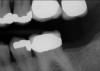

Fig 2. In 2016 patient No. 1 manifested no alterations of tooth position No. 2.

Figure 2

Fig 1. In 2009 patient No. 1 presented with a missing tooth at site No. 31.

Figure 1

Another consideration is mean vertical displacement of unhampered posterior teeth, which in some studies was minimal: 0.8 mm37 and 0.9 mm30 (Table 1). Yet, there could have been sites where the amount of extrusion was clinically relevant. When Lindskog-Stokland et al assessed the risk of over-eruption using 1 mm as a threshold, they stated there was an odds ratio of 3.3 that unimpeded molars would extrude 1 mm compared to opposed molars.30 Based on their calculations, however, it is unclear which patients with a missing molar are at risk of over-eruption (Figure 1 through Figure 4). Indeed, if susceptible individuals could be identified, then restorative therapy could be initiated to stabilize their occlusion (eg, tooth replacement). Furthermore, odds ratios can be highly misleading, and predictive values would provide clinicians a better perspective as to what percentage of sites may experience significant extrusion.41,42